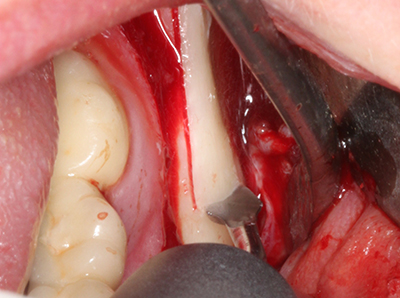

Indication: Preparation near nerves

As noted above, indications for piezosurgery can also be found in the field of conservative dental surgery. Special working tips simplify the exposure of root tips and make it easier to protect nerves and sinus mucous membranes, particularly in the lower premolar and upper posterior tooth regions. Angled diamond tips are used to precisely prepare the resection cavity for the retrograde root filler material for unsealed apical obturation. The ultrasonic technology means the tips can be very slender, which improves the view and the size of the access cavity. As a result, the application of ultrasonic surgery for this indication is one of the standard procedures for apical resection (Del Fabbro, Tsesis et al. 2010, Scarano, Artese et al. 2012).

Indication: Apical resection

When surgical procedures are performed on bone in the immediate vicinity of sensitive structures such as blood vessels or nerves, rotary instruments pose a significant risk of iatrogenic injury. Piezoelectric devices can be helpful for preparation of bone covers and removal of hard tissue close to nerves, particularly for exposure of nerves after iatrogenic injury but also during nerve lateralization for resective and reconstructive procedures or implant placement (Fig. 17-20). Light contact between the piezotip and the nerve does not generally result in damage but proceeding incautiously with saw-like motions or attachments where a residual bone substrate remains may cause temporary or even permanent nerve damage. However, the risk of damage is considered to be substantially lower than when using saws or milling instruments (Pereira, Gealh et al. 2014).